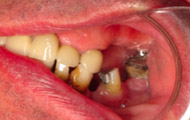

Exemple d’une réhabilitation complète implantaire

Situation clinique initiale